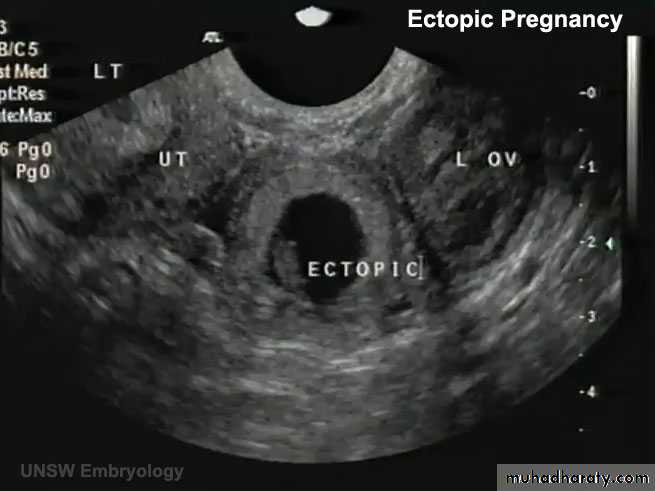

ECTOPIC PREG (EXTRAUTERINE PREG):

- 95% …. Uterine tube… and mostly in the ampula

ABNORMAL IMPLANTATION

Abnormal implantation sites of the blastocyst.

1, implantation in the abdominal cavity. The ovum most frequently implants in the rectouterine cavity (Douglas’ pouch) but may implant at any place covered by peritoneum.2, implantation in the ampullary region of the tube.

3, tubal implantation.

4, interstitial implantation, that is, in the narrow portion of the uterine tube.

5, implantation in the region of the internal os, frequently resulting in placenta previa.

6, ovarian implantation.

• A 23-year-old woman consulted her physician about severe right lower abdominal pain. She said that she had missed two menstrual periods. A diagnosis of ectopic pregnancy was made.

What techniques might be used to enable this diagnosis?

What is the most likely site of the extrauterine gestation (pregnancy)?

How do you think the physician would likely treat the condition?